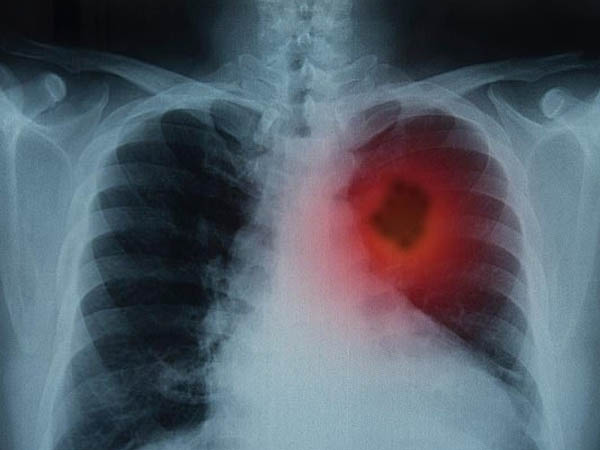

World Cancer Day: घर बैठे फिंगर टेस्ट से लंग कैंसर के बारे में पता लगाएं, ये हैं सिंपल ट्रिक

एक सिम्पल फिंगर टेस्ट जो आप स्वयं घर बैठे कर सकते हैं, इस टेस्ट के जरिए आप लंग कैंसर जैसी गंभीर बीमारी का पता लगा सकते हैं। यूके की कैंसर रिसर्च सेंटर का यह दावा है कि फिंगर क्लबिंग टेस्ट से आप यह पता लगा सकते हैं कि आपको लंग कैंसर यानी फेफड़ों का कैंसर है या नहीं। जानिए कैसे?

फेफड़ों का कैंसर क्या है?

फेफड़े का कैंसर सबसे आम और गंभीर प्रकार के कैंसर में से एक है। फेफड़ों के कैंसर के शुरुआती चरणों में आमतौर पर कोई संकेत या लक्षण नहीं होते हैं, लेकिन जिन लोगों में ये कैंसर होता हैं। उनमें धीरे-धीरे ये लक्षण विकसित होने लगते हैं।